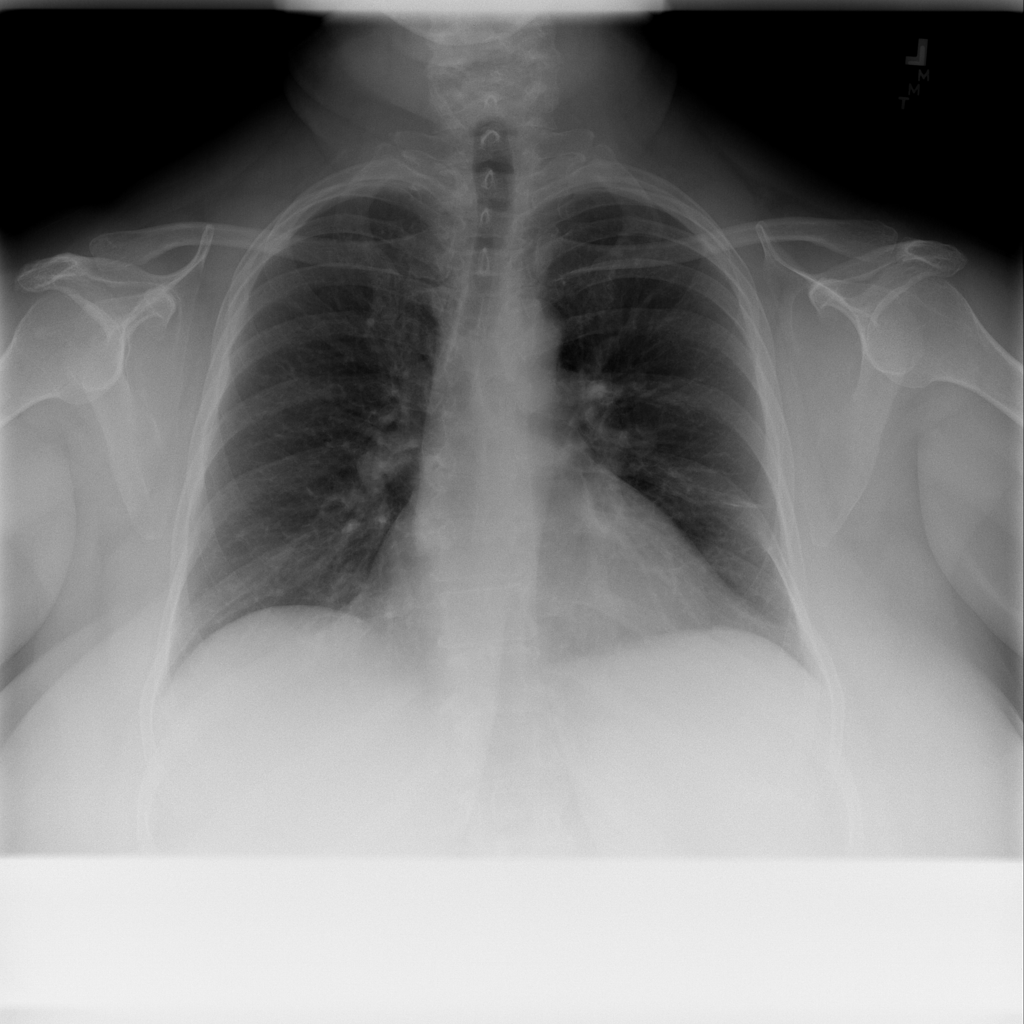

Cardiomegaly

Cardiomegaly means the heart appears enlarged on the chest X-ray. It is a descriptive imaging finding that can be related to heart strain, chronic pressure or volume changes, or even projection effects.

Showing up to 90 reference images for Cardiomegaly.

PAT-AE5C · IMG-000Cardiomegaly

PAT-AE5C · IMG-000

PA